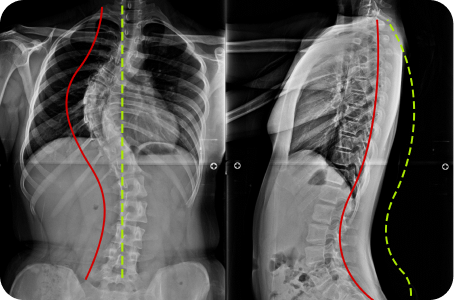

3차원 척추교정이란?

척추의 틀어진 방향과 휘어진 각도는 사람마다 모두 다릅니다.

옆, 앞, 뒤가 각자 틀어지고 꼬인 척추의 변형은 각도와 방향 모두를 고려한

3차원 척추 교정으로 바로잡아야 합니다.

정면, 측면 시각에서 틀어진 방향

척추 만곡의 각도

척추뼈 마디의 회전 변형